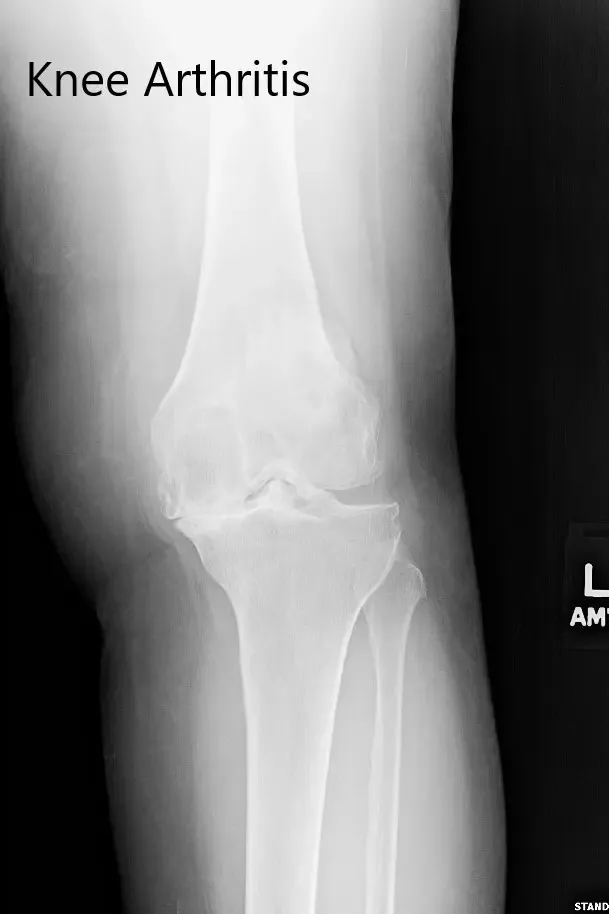

Los estudios de imagen revelaron osteoartritis bilateral severa. La rodilla izquierda estaba peor que la derecha. Teniendo en cuenta el dolor de rodilla limitante en el estilo de vida del paciente, se le recomendó un reemplazo total de rodilla izquierdo. Los riesgos, beneficios y alternativas se discutieron extensamente con el paciente y su hijo. Decidió seguir adelante con el procedimiento.

Radiografía preoperatoria de la rodilla izquierda que mostró osteoartritis severa en las vistas anteroposterior y lateral.